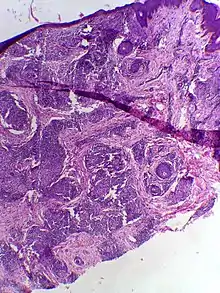

| Skin biopsy in tuberculoid leprosy showing multiple peri-appendageal granulomas. | |

Tuberculoid leprosy is a form of leprosy characterized by solitary skin lesions that are asymmetrically distributed with few lesions and well demarcated edges. There is also early and marked nerve damage. It tends to heal spontaneously.[1]: 345 Tuberculoid leprosy is characterized by the formation of epithelioid cell granulomas consisting of a large number of epithelioid cells. In this form of leprosy, Mycobacterium leprae are either absent from the lesion or occur in very small numbers. This type of leprosy is the most benign and the least contagious.[2][3]